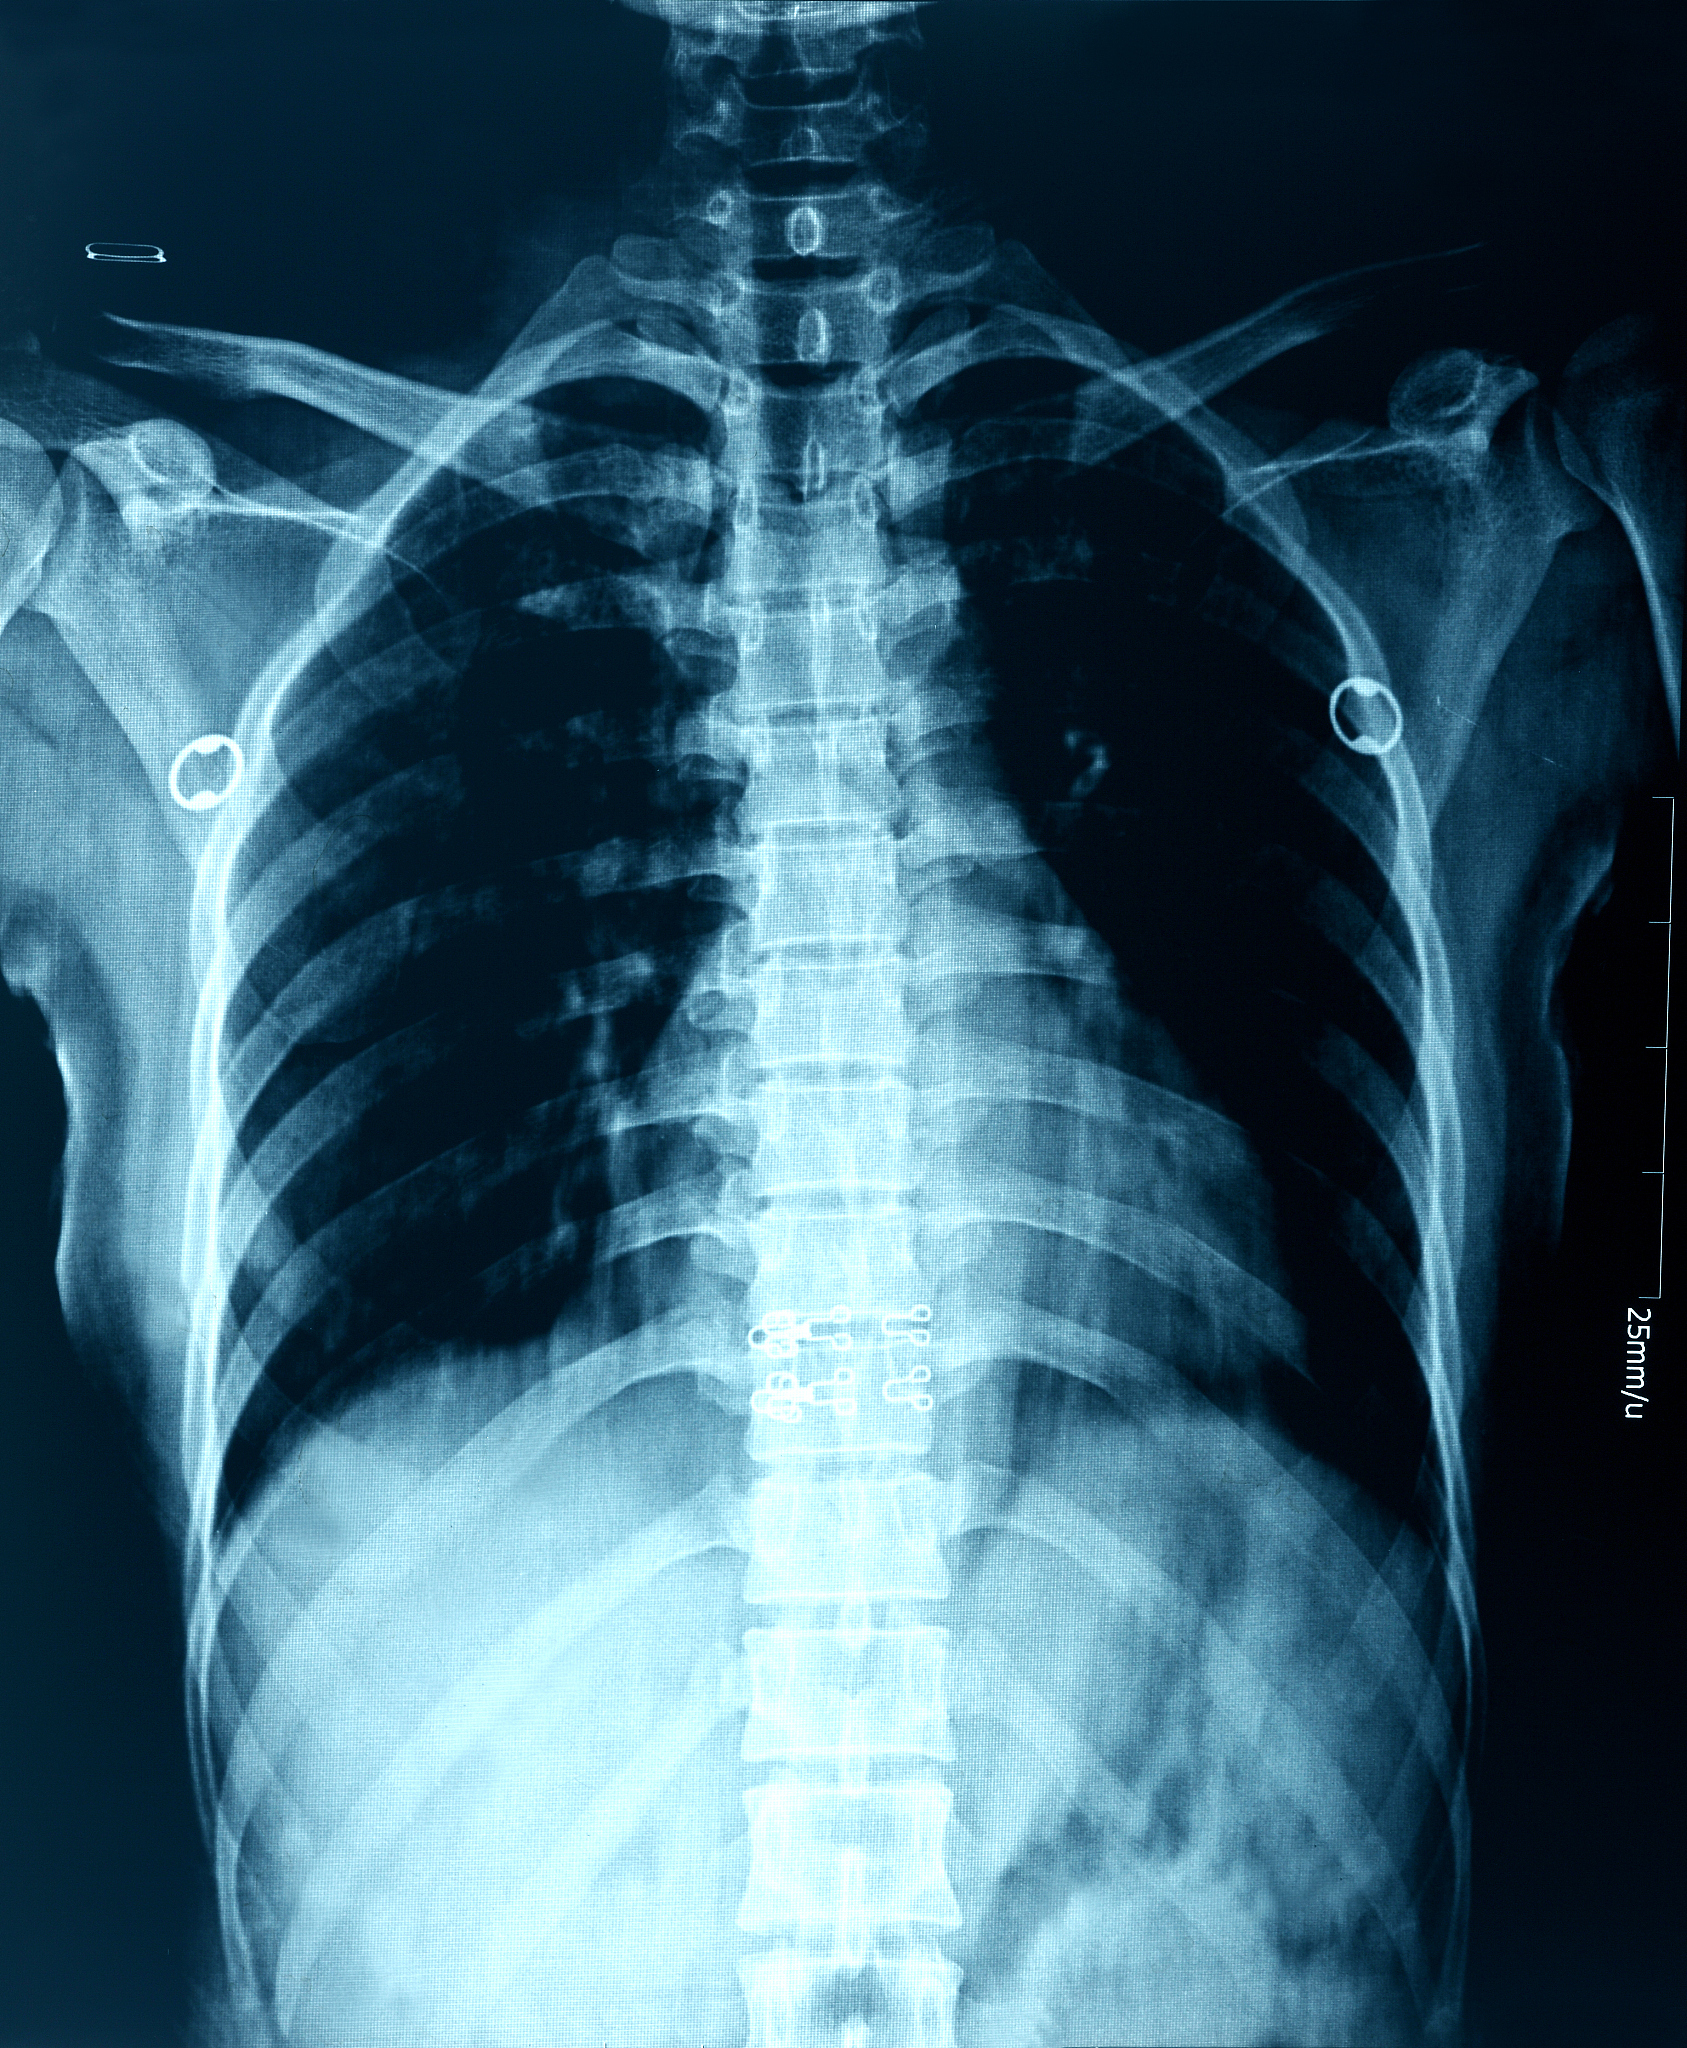

胸部肋骨骨裂是指胸部肋骨发生裂纹或骨折。这种情况对个体的影响会因程度和具体症状而异,但一般来说,胸部肋骨骨裂可能对人产生一定的影响。

胸部肋骨骨裂:影响大吗?症状及治疗